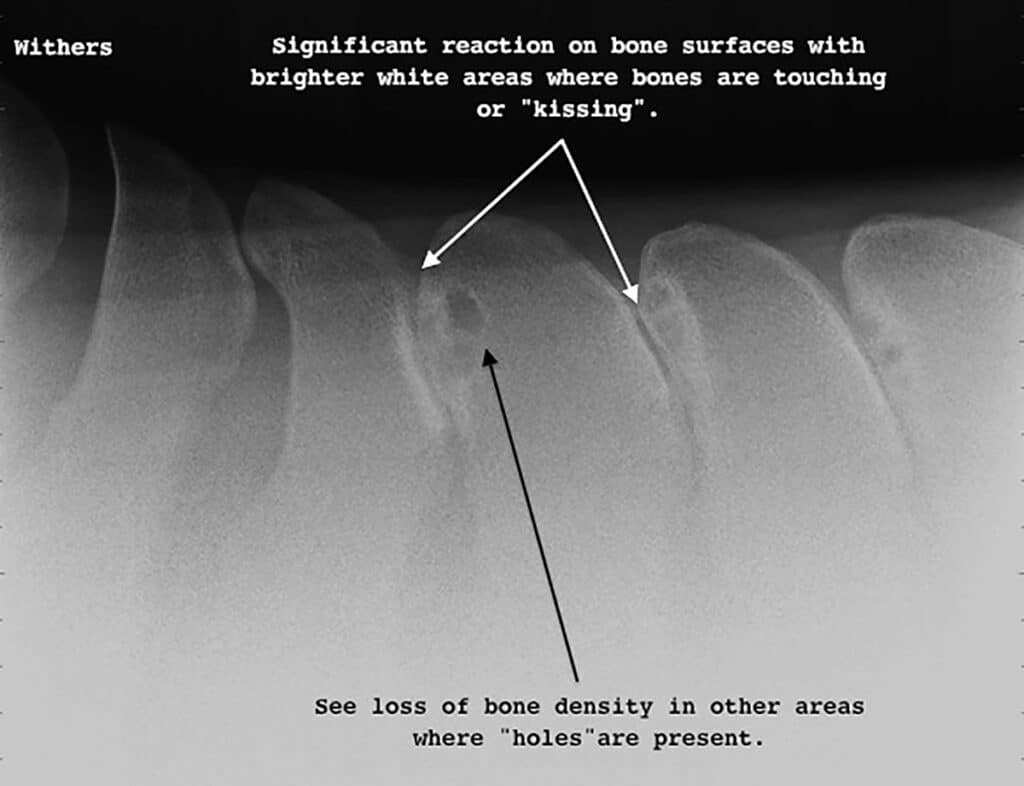

Severe kissing spines where there is significant reaction on the bone surfaces and also a loss of bone density.